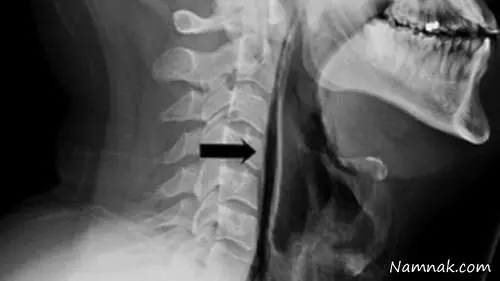

این مرد می گوید بعد از عطسه کردن به این شکل نادرست احساس کرده چیزی در گلویش "ترکیده" و بلافاصله دچار درد شدید و دشواری در تکلم و حتی قورت دادن آب دهانش شده برای همین برای معاینه و درمان به بیمارستان مراجعه کرده است. زمانیکه پزشکان او را معاینه کردند متوجه تورم شدید و درد در ناحیه گردن و گلوی او شدند ، تصویری برداری با اشعه ایکس نشان داد در اثر پارگی ایجاد شده هوا از نای این فرد وارد بافت گلو می شود و علت درد و مشکل در بلع نیز همین بوده است.